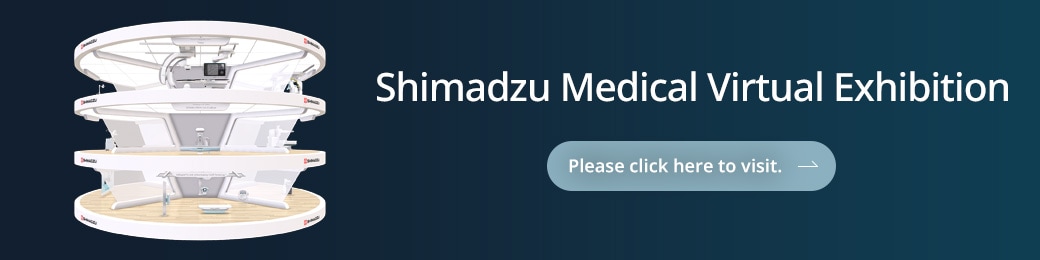

“unity” concept

Trinias provides a patient-centered experience, leaving operators free from worry so they can easily perform all types of interventional procedures. Trinias unity edition sets the bar high with improved functionality with new hardware and software features that provide a simple workflow for cardiac and vascular procedures from head to toe. The system uses Intelligent Design to provide Intelligent Care in minimally invasive procedures. Our technology provides solution to the imaging problems that you face every day.

unity: unlimited intelligent technology